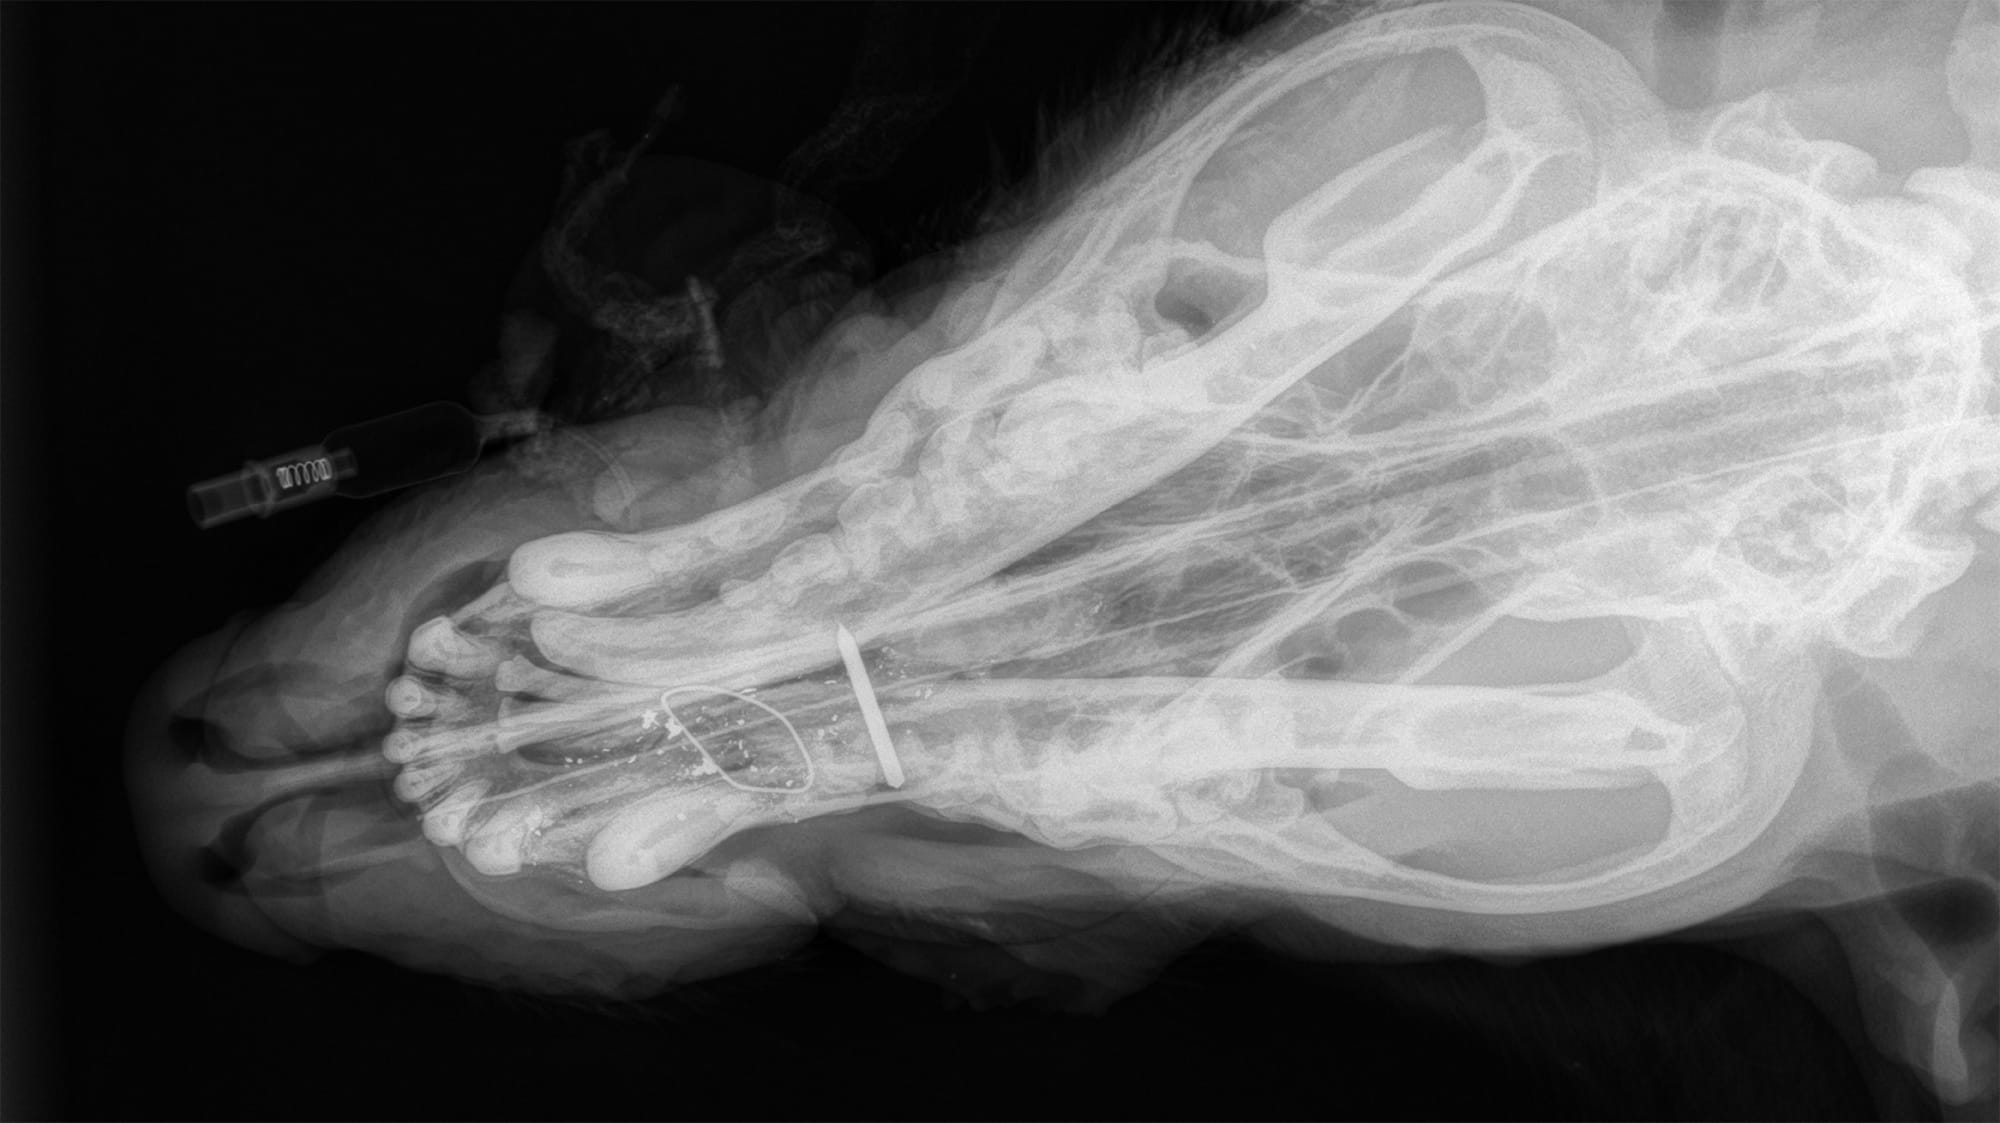

Brutus had been shot in the face and had damage to his canine tooth, the bone of the mandible, and had pieces of bone and bullet throughout his face. Several of his teeth had to be removed, as a well as pieces of bone and bullet, which could cause infection if left untreated. The team removed the injured tissue and affected teeth, then wired his jaw to stabilize his mouth and reconstructed gum tissue. Brutus was under anesthesia for 45 minutes, but his vital signs stayed stable and by 10:30 p.m., the surgery was complete and he was resting.